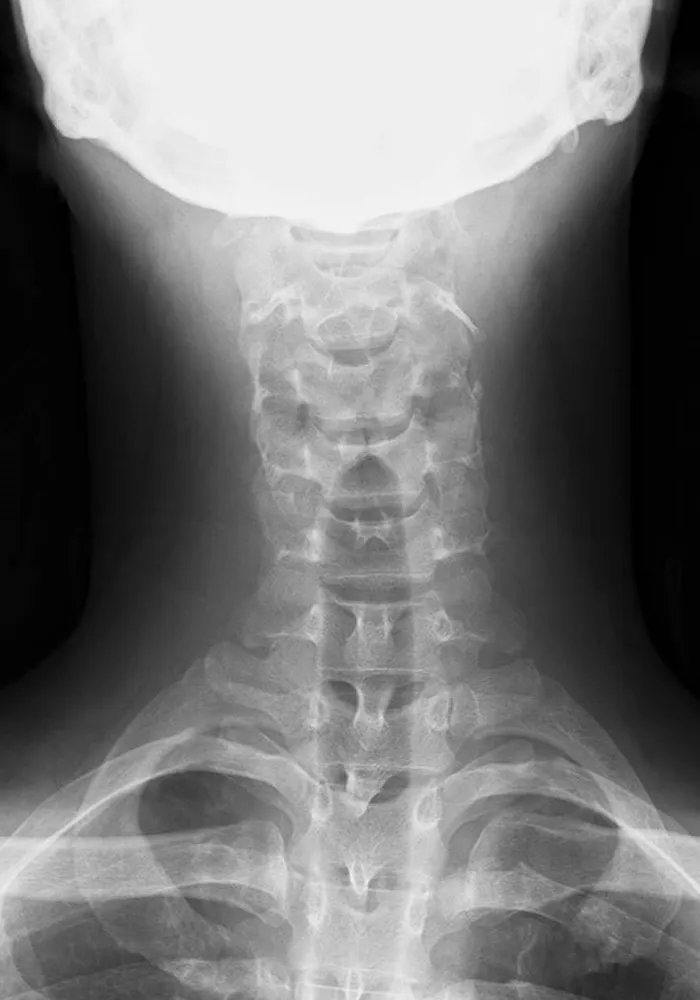

一般撮影

一般撮影は診断目的とする部分にX線を照射して撮影を行う検査です。X線は体内を通過する際に骨や筋肉、内臓などの組織により吸収される量が変化するので、透過したX線量の差を画像化したものがレントゲン写真となります。

当院の一般撮影室は 2室 あり、いずれも フラットパネルディテクタ(FPD)対応 の最新機器を導入しています。FPDを用いることで、従来よりも少ないX線量で効率的に撮影でき、より高画質な画像を得ることが可能です。これにより、患者様の被ばく線量をできる限り低減しつつ、迅速で正確な診断に役立てています。